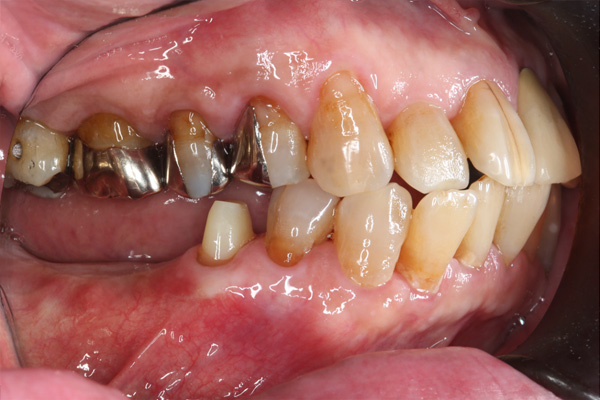

| 年代・性別 | 50代 男性 |

|---|---|

| 主訴 | 右下の歯が割れてしまったのでインプラントをして欲しい |

| 治療期間 | 約6ヶ月 |

| 費用 | 1,100,000円 |

| 治療内容 | インプラント、骨造成、結合組織移植、セラミック修復 |

| 治療に伴うリスク | インプラント周囲炎 セラミックの破折、脱離 |

*キャンセルポリシーをご一読のうえご予約ください